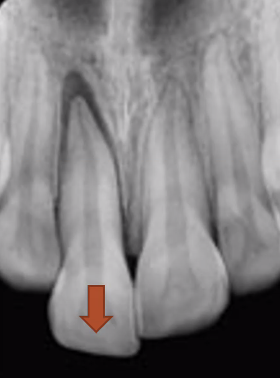

intrusion

tooth travels apically into the socket

poorest prognosis

high degree of damage to neurovascular bundles at apex of tooth, which gets squashed